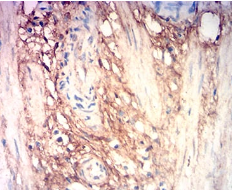

COL3A1 Mouse Monoclonal antibody[8C1G1]

This gene encodes the pro-alpha1 chains of type III collagen, a fibrillar collagen that is found in extensible connective tissues such as skin, lung, uterus, intestine and the vascular system, frequently in association with type I collagen. Mutations in this gene are associated with Ehlers-Danlos syndrome types IV, and with aortic and arterial aneurysms. Two transcripts, resulting from the use of alternate polyadenylation signals, have been identified for this gene.

Immunogen:    Purified recombinant fragment of human COL3A1 (AA: 24-153) expressed in E. Coli.

IHC    1/200 - 1/1000